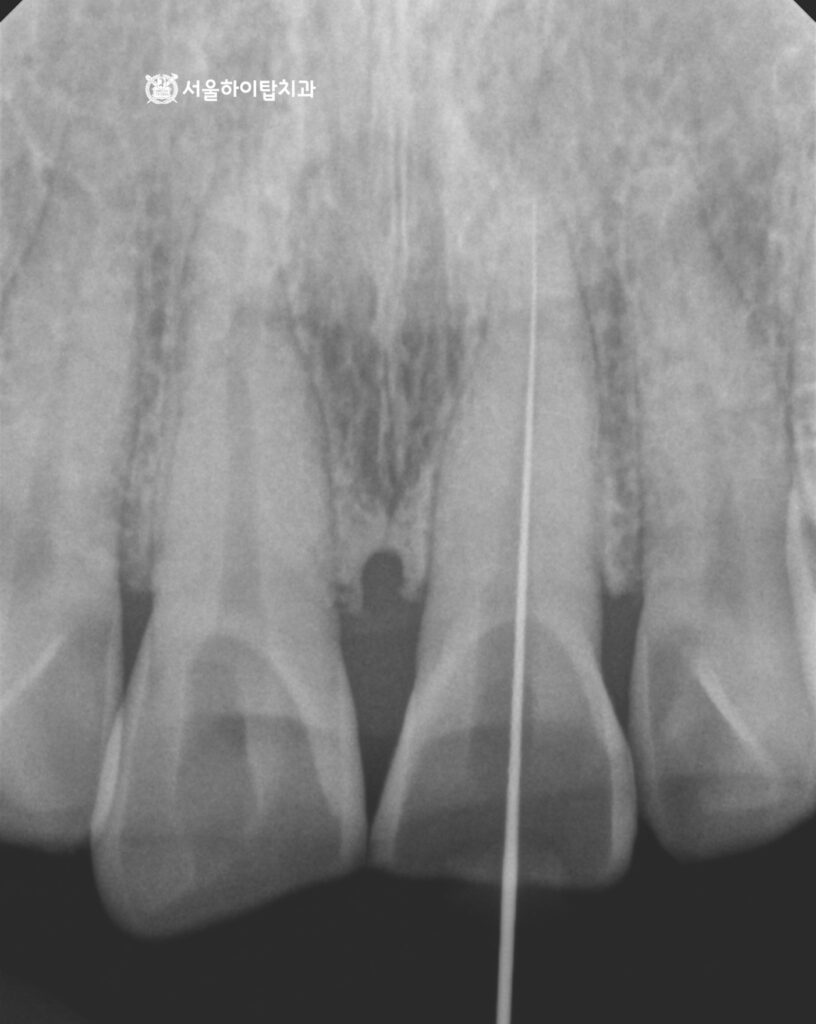

앞니 설면, 즉 혀 쪽에서 바라본 모습입니다.

해당 부위에서 파절과 마모 소견이 함께 관찰되며,

이 중에서도 국소적인 파절보다는 전반적인 마모가 더 뚜렷한 상태로 보입니다.

이와 같은 형태의 교모는 보통 교합력이

어금니가 아닌 앞니로 집중될 때 흔히 나타납니다.

다만, 앞서 엑스레이에서 어금니에는 큰 병적 소견이 관찰되지 않았기 때문에,

부평 치과 에서는 다음과 같은 두 가지 가능성을 중심으로 원인을 고려해 볼 수 있습니다.

- 이갈이, 이 악물기(브럭시즘) + 전치 접촉

이갈이 습관이 있더라도 정상적인 교합에서는

어금니가 먼저 접촉하여 힘을 분산시키게 됩니다.

하지만 앞니가 먼저 닿는 교합 구조라면,

수면 중 반복되는 마찰이 전치부에 집중되면서

특히 앞니 설면을 중심으로 한 수평 교모가 빠르게 진행될 수 있습니다. - 어금니 지지 부족의 ‘보상 작용’

겉보기에는 어금니가 멀쩡해 보이더라도,

교합 접촉이 약하거나 기능적인 지지가 충분하지 않은 경우에는

저작 시 앞니가 이를 보완하는 역할을 하게 됩니다.

이 과정이 반복되면 앞니에 과도한 하중이 가해지게 되고,

결과적으로 마모가 빠르게 진행되는 양상을 보일 수 있습니다.